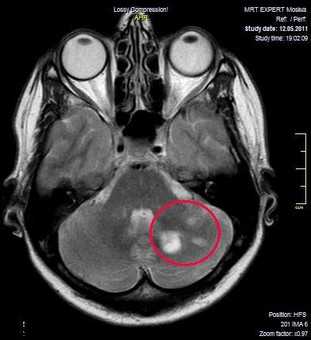

Классический пример МРТ снимков головного мозга показан на рисунках ниже. Магнитно-резонансная томография выполняется в поперечной (или аксиальной - рисунок снизу) и продольной (или сагиттальной — рисунок сверху) плоскостях.

Исследование выполняется в нескольких режимах. Основные из них Т1 и Т2. Изображения, полученные в данных режимах, часто также называют Т1-взвешенными или Т2-взвешенными снимками. Изображения, показанные выше, сделаны в Т1-режиме.

Главное отличие этих режимов - в том, как на снимках отображается жидкость и воздух. В Т1 режиме ткани, содержащие большое количество воды, имеют более темную окраску, в то время как в Т2 режиме они яркие, светлые. Это легко понять, посмотрев на снимки выше - глазные яблоки визуализируются в виде светлых парных округлых образований с одной стороны яркие и светлые, с другой - темные. Следовательно, снимок справа сделан в Т1 режиме, снимок слева - в Т2. Также существует разница в том, как в этих режимах отображается серое вещество головного мозга. В Т2 режиме оно светлее, чем белое вещество.